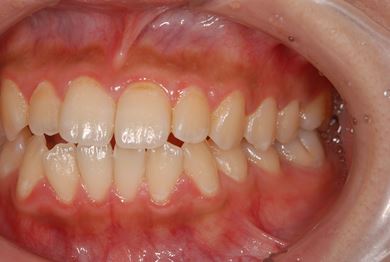

治療前

• 治療前